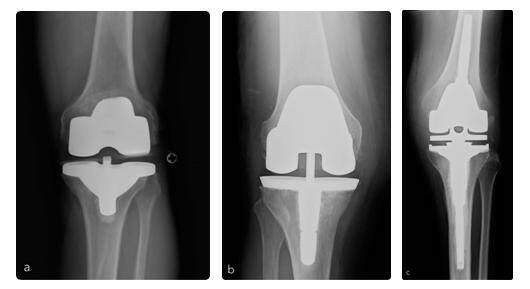

Protesi di ginocchio: precisione, planning pre-operatorio e chirurgia personalizzata

La protesi di ginocchio rappresenta oggi una delle procedure più efficaci della chirurgia ortopedica per il trattamento del dolore e della disabilità legati all’usura articolare.

Protesi totale o monocompartimentale?

Non tutti i pazienti hanno bisogno di una protesi totale di ginocchio. In casi selezionati, quando l’usura interessa un solo compartimento e i legamenti sono conservati, può essere indicata una protesi monocompartimentale.

La protesi totale resta però la soluzione più frequente nei quadri di artrosi avanzata o diffusa, perché consente di trattare in modo più completo la degenerazione articolare e le eventuali deformità associate.